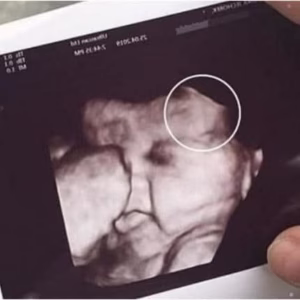

Doctors couldn’t believe what they saw during the ultrasound

The Baby Born with a Crown of HairWhen 29-year-old Emily Foster, from Kent, England, arrived for her routine 20-week pregnancy scan, she expected the usual joy —…